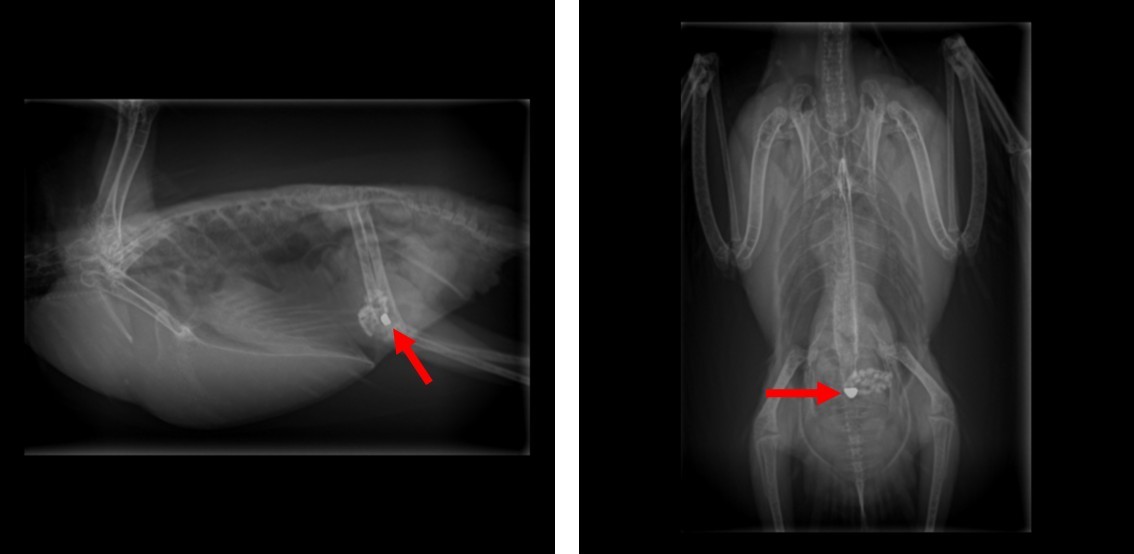

■鉛中毒

鉛はかなり強い中毒を起こします。家庭内では、カーテンウエイト(カーテンの裾に入れる線状のおもり)などに鉛が使用されていることがあり、それを齧って中毒を起こす事例があります。症状は嘔吐などの消化器症状、翼の下垂(かすい)、足の麻痺、痙攣などの神経症状、腎不全症状などを示すことがあります。特徴的な変化として、濃緑色便を排せつすることがあります。